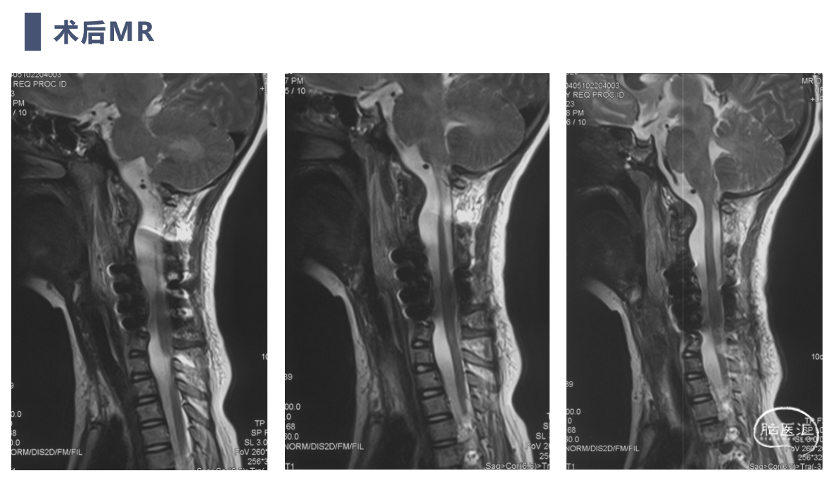

术后MRI

术后复查患者复位满意,颈痛及神经症状消失,但此类患儿骨性结构发育异常,需要密切随诊,观察有无近端或远端交界性后凸发生。

双向牵引后,患者后方小关节仍存在一定绞锁,首先行后路手术,充分松解后方绞锁的关节突。再行前路手术,矫正后凸畸形,前路手术时因患者骨量极少,单纯前路螺钉复位力量弱,借助提拉工具完成良好复位。最后翻身行后路手术完成C2-7后路固定,因患者多数侧块发育异常,双侧C4-5无法置钉,应用椎板钩固定,双侧C2椎弓根直径只有3.2mm,但成功置入了两颗3.5mm螺钉。